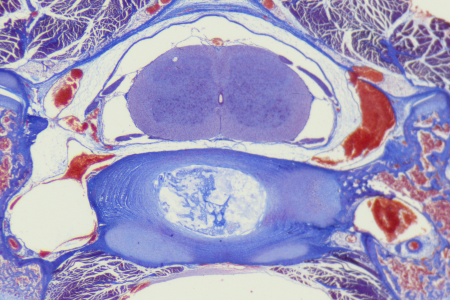

應用範例